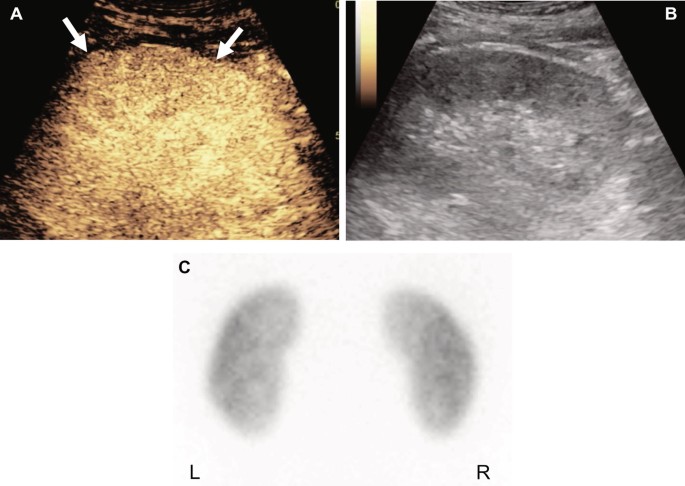

When the DMSA scan was used as the reference standard, sensitivity, positive predictive value (PPV), and negative predictive value (NPV) were fairly high at 80.0% or higher. Specificity was lower at 71.4%. When CT was used as the reference standard, sensitivity, specificity, PPV, and NPV were 80.0% or higher. The sensitivity of CEUS was higher (86.8–87.5%) than the specificity of CEUS (71.4–80.0%). Diagnostic accuracy of CEUS with either the DMSA scan or CT as the reference standard was 80.3% and 84.6%, respectively. A representative true-positive case is illustrated in Fig. 1.

A 9-month-old female with acute pyelonephritis. The DMSA scan image (A) shows multifocal cortical defects (arrows) in the left kidney (image rotated so that it corresponds to the CEUS image). The CEUS image on the longitudinal plane (B) shows correlating areas of cortical perfusion defects (arrows). The gray-scale image of CEUS (C) shows decreased echogenicity in the areas with perfusion defects.